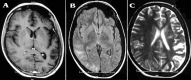

Authors describe the case of a 16-year-old girl who presented with fever, tonic-clonic seizures, unequal arm blood pressures and pulselessness in the left upper limb. On examination, there was a systolic bruit over umbilical region, a pansystolic murmur of mitral regurgitation was found. Neurological examination was normal except for an asymmetry in brain hemicircumference one side compared with the other. She has borderline intelligence (IQ 70) according to Wechsler Adult Performance Intelligence Scale. Magnetic resonance imaging (MRI) of brain revealed atrophic of left cerebral hemisphere with mildly ventricular dilatation, prominent paranasal and mastoid air cells, suggestive of Dyke-Davidoff-Masson syndrome (DDMS). Conventional angiography showed narrowed left internal carotid artery. There was also stenosed brachial artery, absent left renal artery with narrowed infrarenal abdominal aorta. The patient was put on antihypertensive drugs. We hypothesise that Takayasu arteritis and related vascular occlusion is the cause of her acquired cerebral changes.